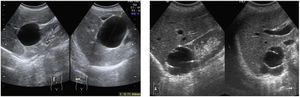

La ecografía por vía abdominal permite no solo la medición de tamaño prostático, es decir los ejes y el volumen, sino también la forma de crecimiento, valorando si es un crecimiento uniforme o principalmente del lóbulo medio.

Para la medición de tamaño prostático se utiliza la doble pantalla para poder medir en el corte longitudinal el eje craneocaudal y en el corte transversal el eje anteroposterior y el transversal de la próstata, y de esta manera poder hallar el volumen prostático. La clasificación del crecimiento prostático es5 (fig. 3 y video 4):

- -

Grado I: Eje AP 30-38mm y volumen 20-36cc

Grado II: Eje AP 38-45mm y volumen 36-60cc

Grado III: Eje AP 45-55mm y volumen 60-90cc

Grado IV: Eje AP>55mm y volumen >90cc

En los casos en los que hay un crecimiento principalmente del lóbulo medio, estas medidas son algo diferentes, ya que el lóbulo medio protruye hacia la luz vesical dando una imagen a veces de lesión intraluminal.

En los casos en los que el crecimiento prostático va asociado a vejiga de lucha encontraremos como datos ecográficos un engrosamiento difuso de las paredes vesicales, con la presencia de divertículos vesicales, visualizados como evaginaciones de la pared, habitualmente con cuello estrecho en los que podemos encontrar en algunas ocasiones litiasis en su interior14.

En algunos pacientes con crecimiento prostático y hematuria de larga evolución se pueden observar coágulos vesicales, visualizados como masas heterogéneas, sólidas, habitualmente redondeadas, que se movilizan con los cambios posturales, lo que determina que no depende de pared vesical y, por tanto, descartar que se trate de una neoplasia vesical.